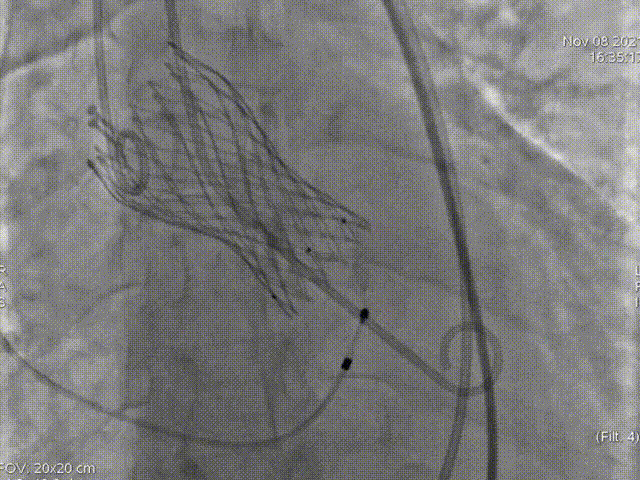

起始释放

第一次释放

位置稍深,选择回收,重新定位释放

第二次起始释放

第二次释放位置良好